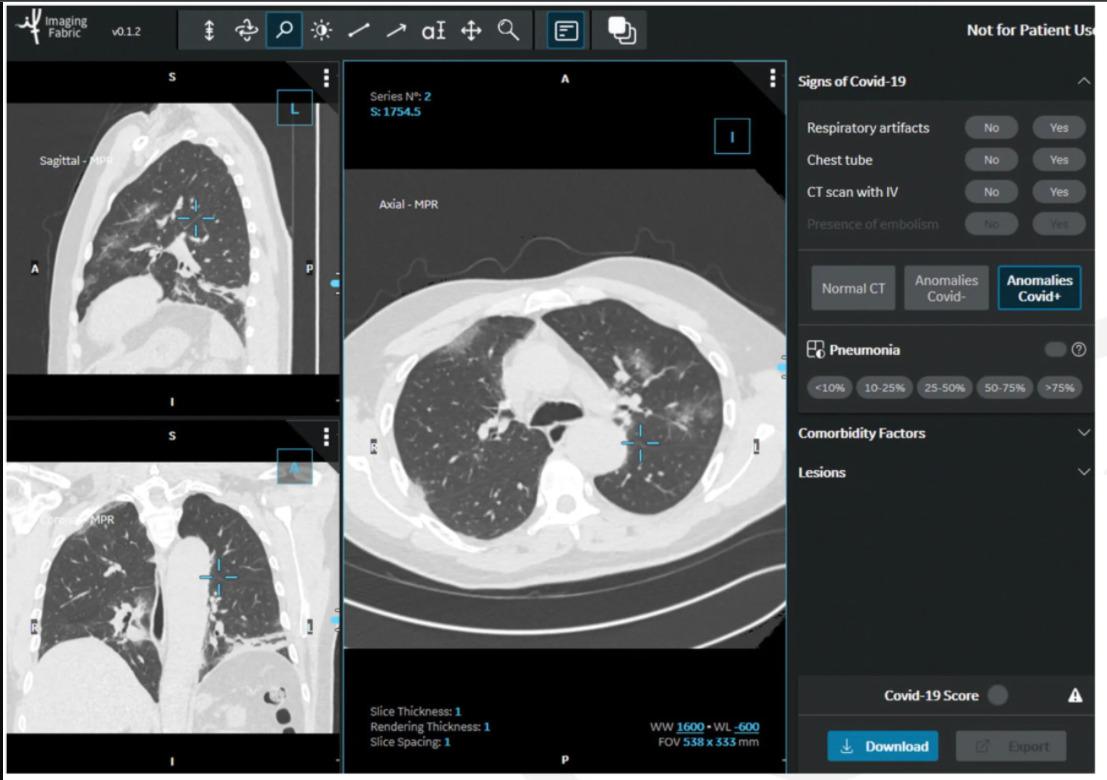

This photo gallery shows the variety of radiological presentations of COVID-19 (SARS-CoV-2) in medical imaging, including computed tomography (CT), radiograph X-rays, ultrasound, echocardiograms and magnetic resonance imaging (MRI). The radiology images show examples of typical COVID pneumonia in the lungs and the numerous complications the virus causes in the body in multiple organs, including the brain, kidneys, heart, abdomen and vascular system.